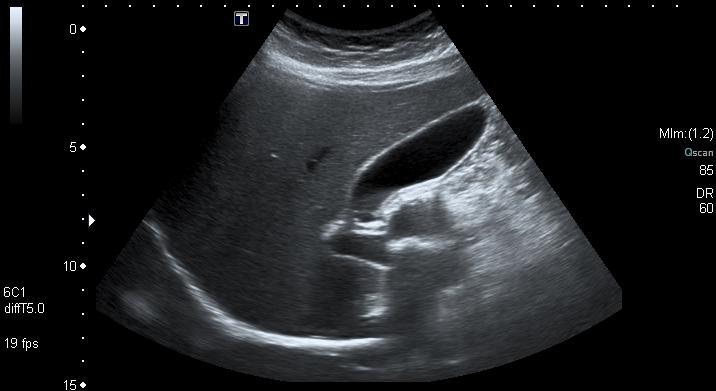

Voir lâaorte avant quâelle ne cĂšde.